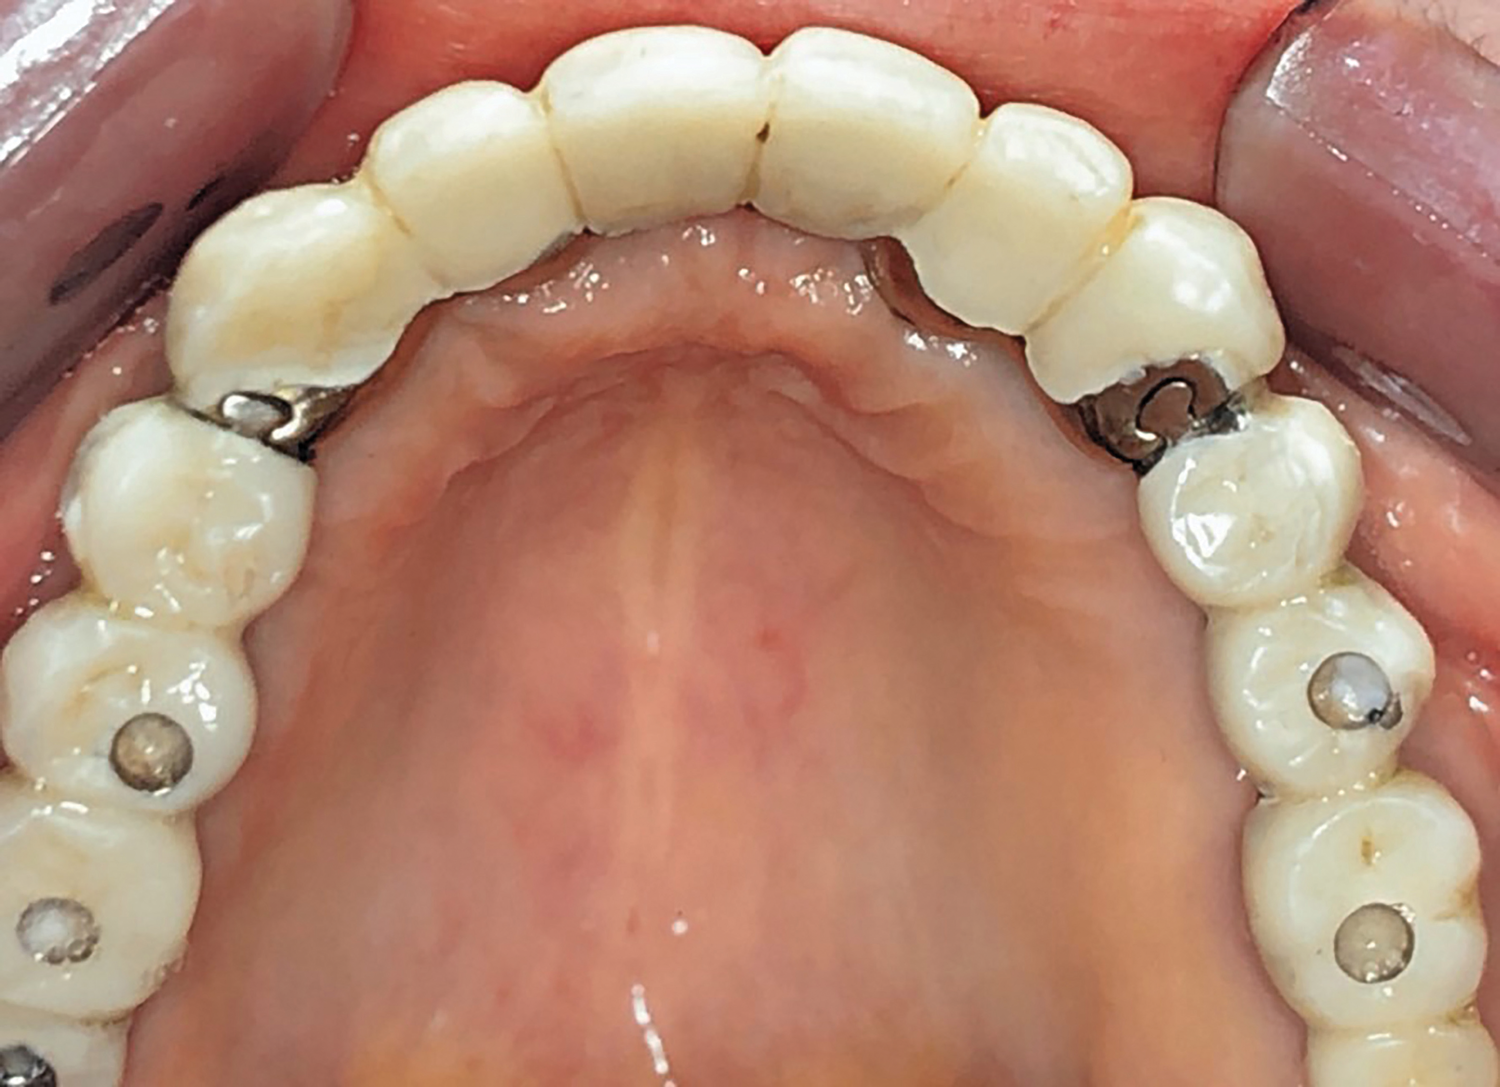

Fig 1. Initial occlusal view of maxillary arch.

Figure 1

Clinical and radiographic examinations were carried out and revealed multiple missing teeth, nonrestorable teeth, periodontal disease, and bone loss (Figure 1 and Figure 2). The final treatment plan that was then proposed to and accepted and signed by the patient included extraction of all remaining teeth in the maxilla, delivery of a provisional fixed restoration supported by six transitional implants, bilateral sinus augmentation, placement of eight to 10 conventional implants, and an implant-supported porcelain-fused-to-metal or hybrid (screw-retained) restoration. For the mandible, the plan included extraction of teeth Nos. 29 and 32 and placement of implants in sites Nos. 18, 19, 20, 29, 30, and 31, with three splinted implant-supported fixed crowns on each side. The patient, however, decided to proceed only with the maxillary restoration and have the mandibular implants and restorations done in private practice.